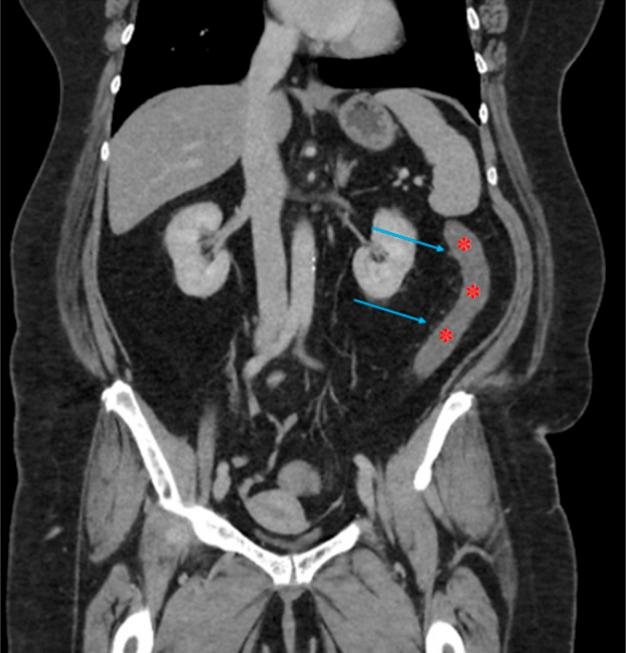

The use of the glucagon-like peptide-1 (GLP-1) and glucose-dependent insulinotropic polypeptide (GIP) receptor agonist tirzepatide has markedly increased for the treatment of weight loss and management of diabetes mellitus. Gastrointestinal adverse effects of GLP-1/GIP agonist therapy, including nausea, vomiting, and constipation, are common. We report a case of colonic ischemia in a 62-year-old woman which developed in association with the use of tirzepatide for weight loss. This report highlights a potential risk relationship between GLP-1/GIP agonist therapy and colonic ischemia and identifies risk factors that should be considered before prescribing tirzepatide.

胰高血糖素样肽-1(GLP-1)和葡萄糖依赖性促胰岛素多肽(GIP)受体激动剂替尔泊肽在减肥和糖尿病管理治疗中的使用显著增加。GLP-1/GIP激动剂疗法的胃肠道不良反应,包括恶心、呕吐和便秘,很常见。我们报告一例62岁女性的结肠缺血病例,该病例与使用替尔泊肽减肥有关。本报告强调了GLP-1/GIP激动剂疗法与结肠缺血之间的潜在风险关系,并确定了在开具替尔泊肽处方前应考虑的风险因素。